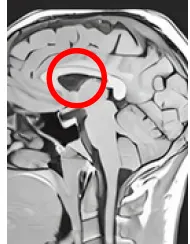

- 人體內的一切都指向一個源點:大腦中心的松果體。

- 就在大腦正中心,即:松果體的位置